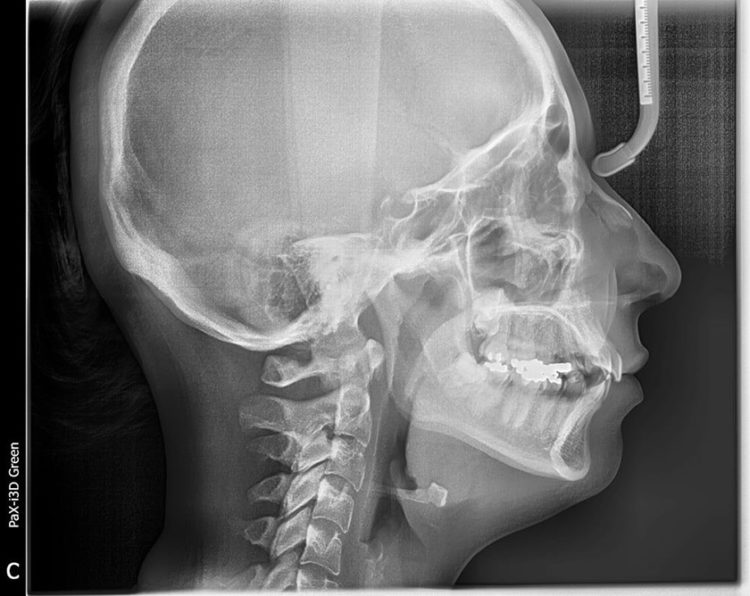

Chụp X-quang răng là một kỹ thuật chẩn đoán hình ảnh về răng, xương và các mô mềm xung quanh răng để tìm ra các vấn đề bệnh lý về miệng, răng và hàm. Thông qua hình chụp phim X-quang, bác sĩ sẽ có những chẩn đoán chính xác về tình trạng răng, mức độ hô móm, cấu trúc xương hàm, răng mọc ẩn như răng khôn cũng như tình trạng bị mất xương không thể quan sát được bằng mắt thường. Ngoài ra chụp X-quang còn được thực hiện để theo dõi sau khi điều trị nha khoa xem có vấn đề gì chưa ổn không.

Để đạt được kết quả niềng răng tốt nhất bác sĩ cần phải có phác đồ điều trị cụ thể đối với từng trường hợp. Thông qua phim chụp X-quang của bạn, bác sĩ sẽ hiểu rõ được đặc điểm xương hàm, trục răng, mức độ lệch lạc, độ cứng chắc của răng. Những điều này nếu chỉ có thăm khám thông thường sẽ không thể hiểu chính xác tình trạng răng và lên được phác đồ điều trị chi tiết.

Thông qua các dữ liệu thu được từ phim X-quang cùng với hình ảnh chụp trong miệng, ngoài mặt, dấu hàm, bác sĩ mới đưa ra được nhận định chính xác về tình trạng răng, hướng dịch chuyển của răng sau khi niềng. Và vì mỗi người có đặc điểm xương răng khác nhau, nên sẽ cần có phác đồ điều trị răng khác nhau.